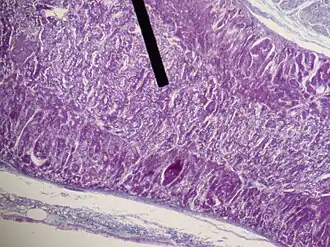

Adrenal medulla (on the pointer) stains lighter than the adrenal cortex, H&E stain | |